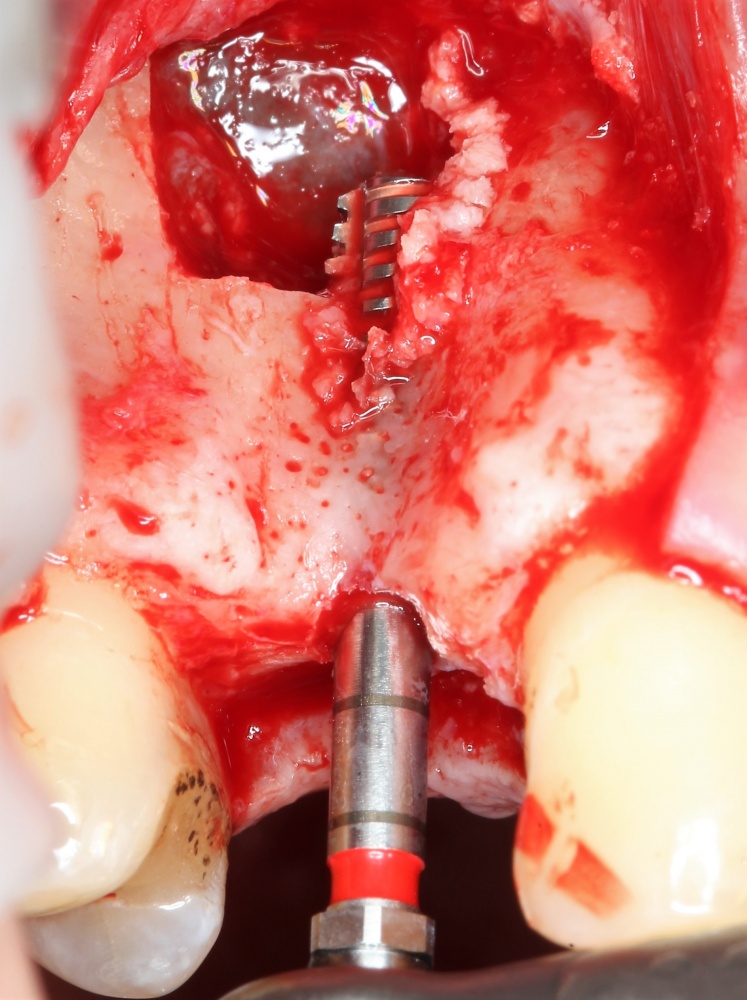

Забор костного фрагмента проводится с наружной косой линии с помощью ультразвукового пьезохирургического инструмента. Ничего сверхнового и супернеобычного тут нет, совершенно стандартная методика. С той лишь разницей, что молоток для этого используют только фашисты и только в гестапо использовать не нужно, всё делается усилием и ловкостью рук.

Нюансы начинаются с обработки принимающего ложа. Да-да, уважаемые друзья, одна из причин некроза блоков, их чрезмерной атрофии и прочих проблем — в отсутствии обработки принимающего ложа. Некоторые делают дырки, но правильнее и эффективнее поступить так:

то есть, просто снять слой кортикальной пластинки с участка, к которому будет фиксироваться костный блок. Почему? Читайте здесь>>.

Вторая особенность — мы не адаптируем и не обрабатываем костный блок invitro, а фиксируем его так, как есть:

после чего обрабатываем — доводим до окончательной формы альвеолярного гребня:

Далее, можем приступить к установке имплантатов. Разумеется. по хирургическому шаблону:

Последняя картинка даёт представление о том, какой объем костной ткани мы «нарастили».

Поскольку принимающее ложе и аутокостный блок конгруэнтны, мы можем отказаться от использования барьерной мембраны. Она не нужна.